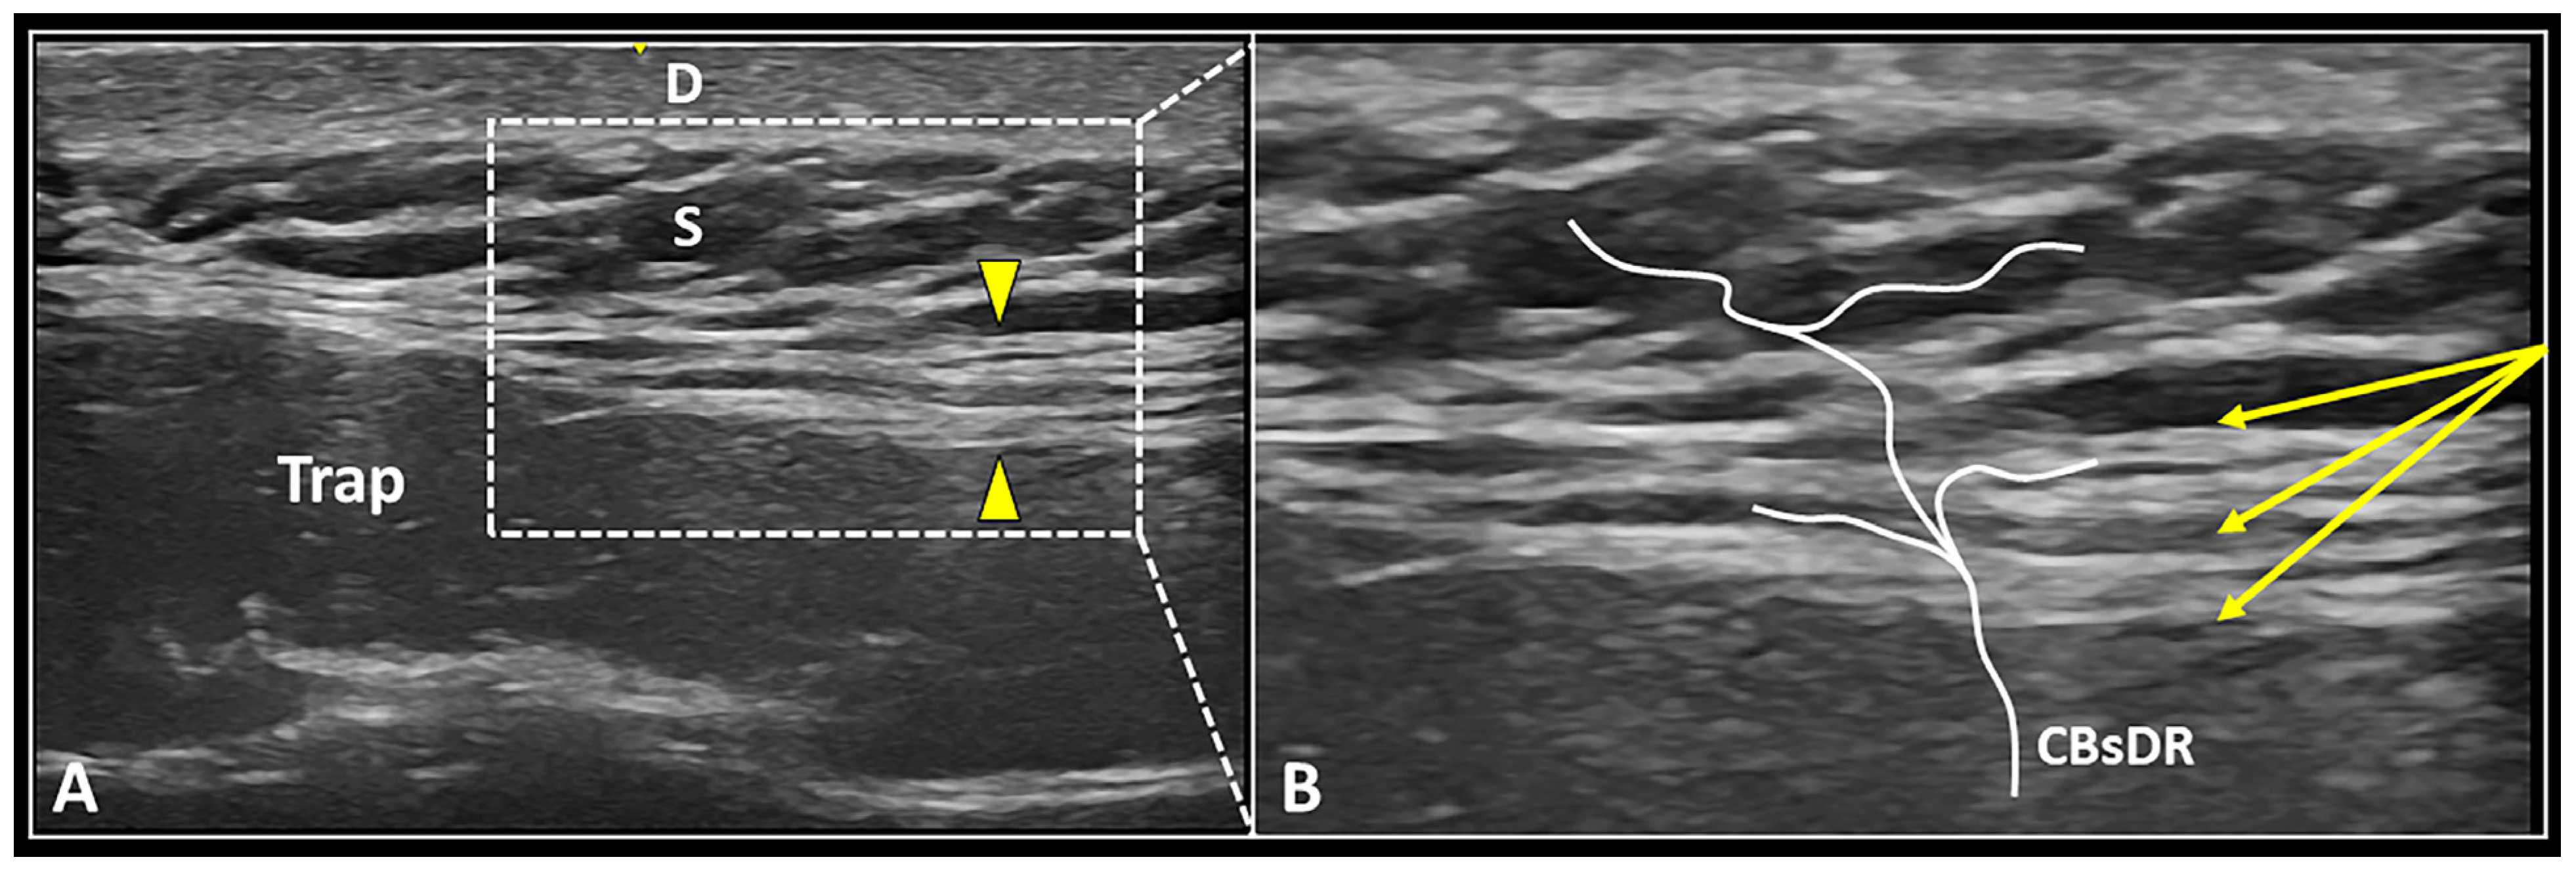

As previously mentioned, the deep fascia is a highly innervated and multi-layered fibrous structure that is extensively crossed by the CBsDR of spinal nerves [31,32]. Normally, the deep fascia presents a hyperechoic fibrillar echotexture (Figure 4), but in pathological conditions, hypoechogenicity, focal thickening, delamination, and perifascial effusion can be considered the most common sonographic findings [46,47].

Figure 4.

US image (A) shows the multi-layered deep fascia (yellow arrowheads) located between the upper fibers of the trapezius muscle (Trap) and the subcutaneous tissue (S). Under real-time US guidance (B), the needle (yellow arrows) can be advanced within the fascial structure, dissecting its different layers and releasing perforating cutaneous branches (CBsDR). D: dermis.

US-guided hydro-dissection of the deep fascia can be considered an “advanced” interventional technique that simultaneously targets the intrafascial free nerve endings and the perforating cutaneous branches alike [25,31]. These tiny neural elements can concomitanly evoke superficial pain over the skin and deep pain mimicking muscle pain [51]. Moreover, layer-by-layer high-volume injection of the deep fascia can be considered a procedure that is potentially useful to restore the intrafascial gliding counteracting the above-quoted fascial densification [24,46]. As regards the technical tips and tricks, a long and flexible needle should be used to better “navigate” through the multiple layers of deep fascia. During both the advancement and retraction phases of the needle, the authors suggest slowly releasing the high-volume mixture to optimize the progressive detachment of the different layers of deep fascia—i.e., the seeding technique [35,48]. Last but not least, multiple back-and-forward movements of the needle within the deep fascia should be performed to better release the intrafascial adhesions in between its multiple layers.